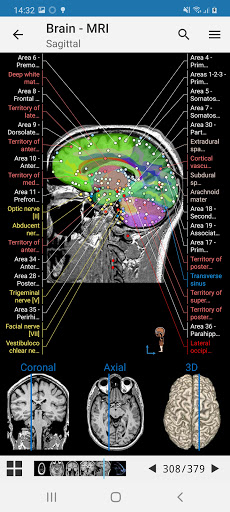

e-Anatomy tiene más de 26 000 imágenes que contienen series de imágenes en vistas axiales, coronales y sagitales, así como radiografías, angiografías, imágenes de disección, gráficos anatómicos e ilustraciones. Todas las imágenes médicas fueron etiquetadas cuidadosamente, más de 967 000 etiquetas disponibles en 12 idiomas, incluida la Terminologia Anatomica latina.

- Desplácese por los conjuntos de imágenes arrastrando el dedo

- Acerque y aleje el zoom

- Toque las etiquetas para mostrar las estructuras anatómicas

- Seleccione las etiquetas anatómicas por categoría

- Localice fácilmente las estructuras anatómicas gracias a la búsqueda de índice